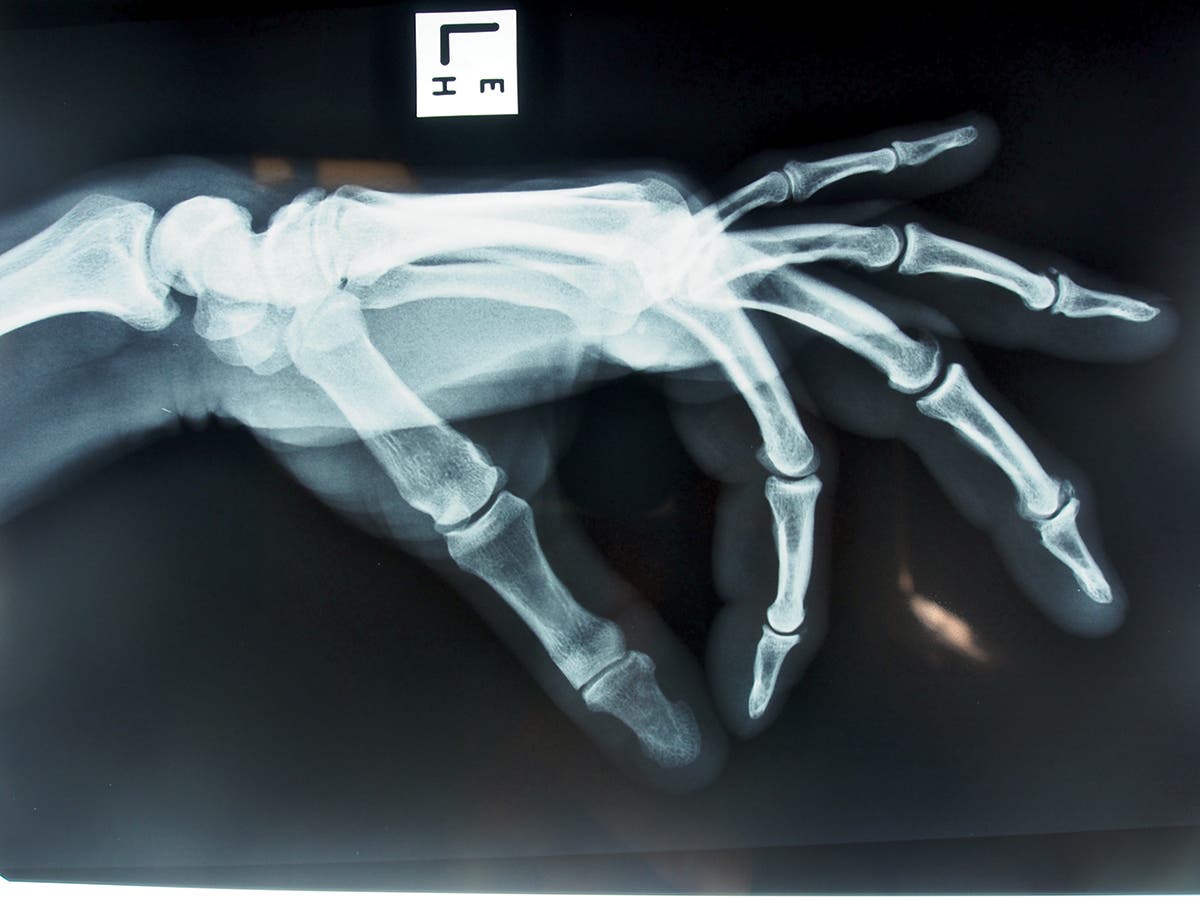

A hand about half a second before it dry-fires off an edge. That kind of force can cause long term joint damage and arthritis. (Photo: Kiff Alcocer)

Glucosamin. The galactic enthusiasm that put glucosamine sulphate (GS) on the shelves of every supermarket virtually overnight has eased somewhat in the last decade, but evidence still firmly points to its ability to ease pain and improve function, with some radiological studies (X-rays) demonstrating that certain GS preparations can slow osteoarthritis progression.